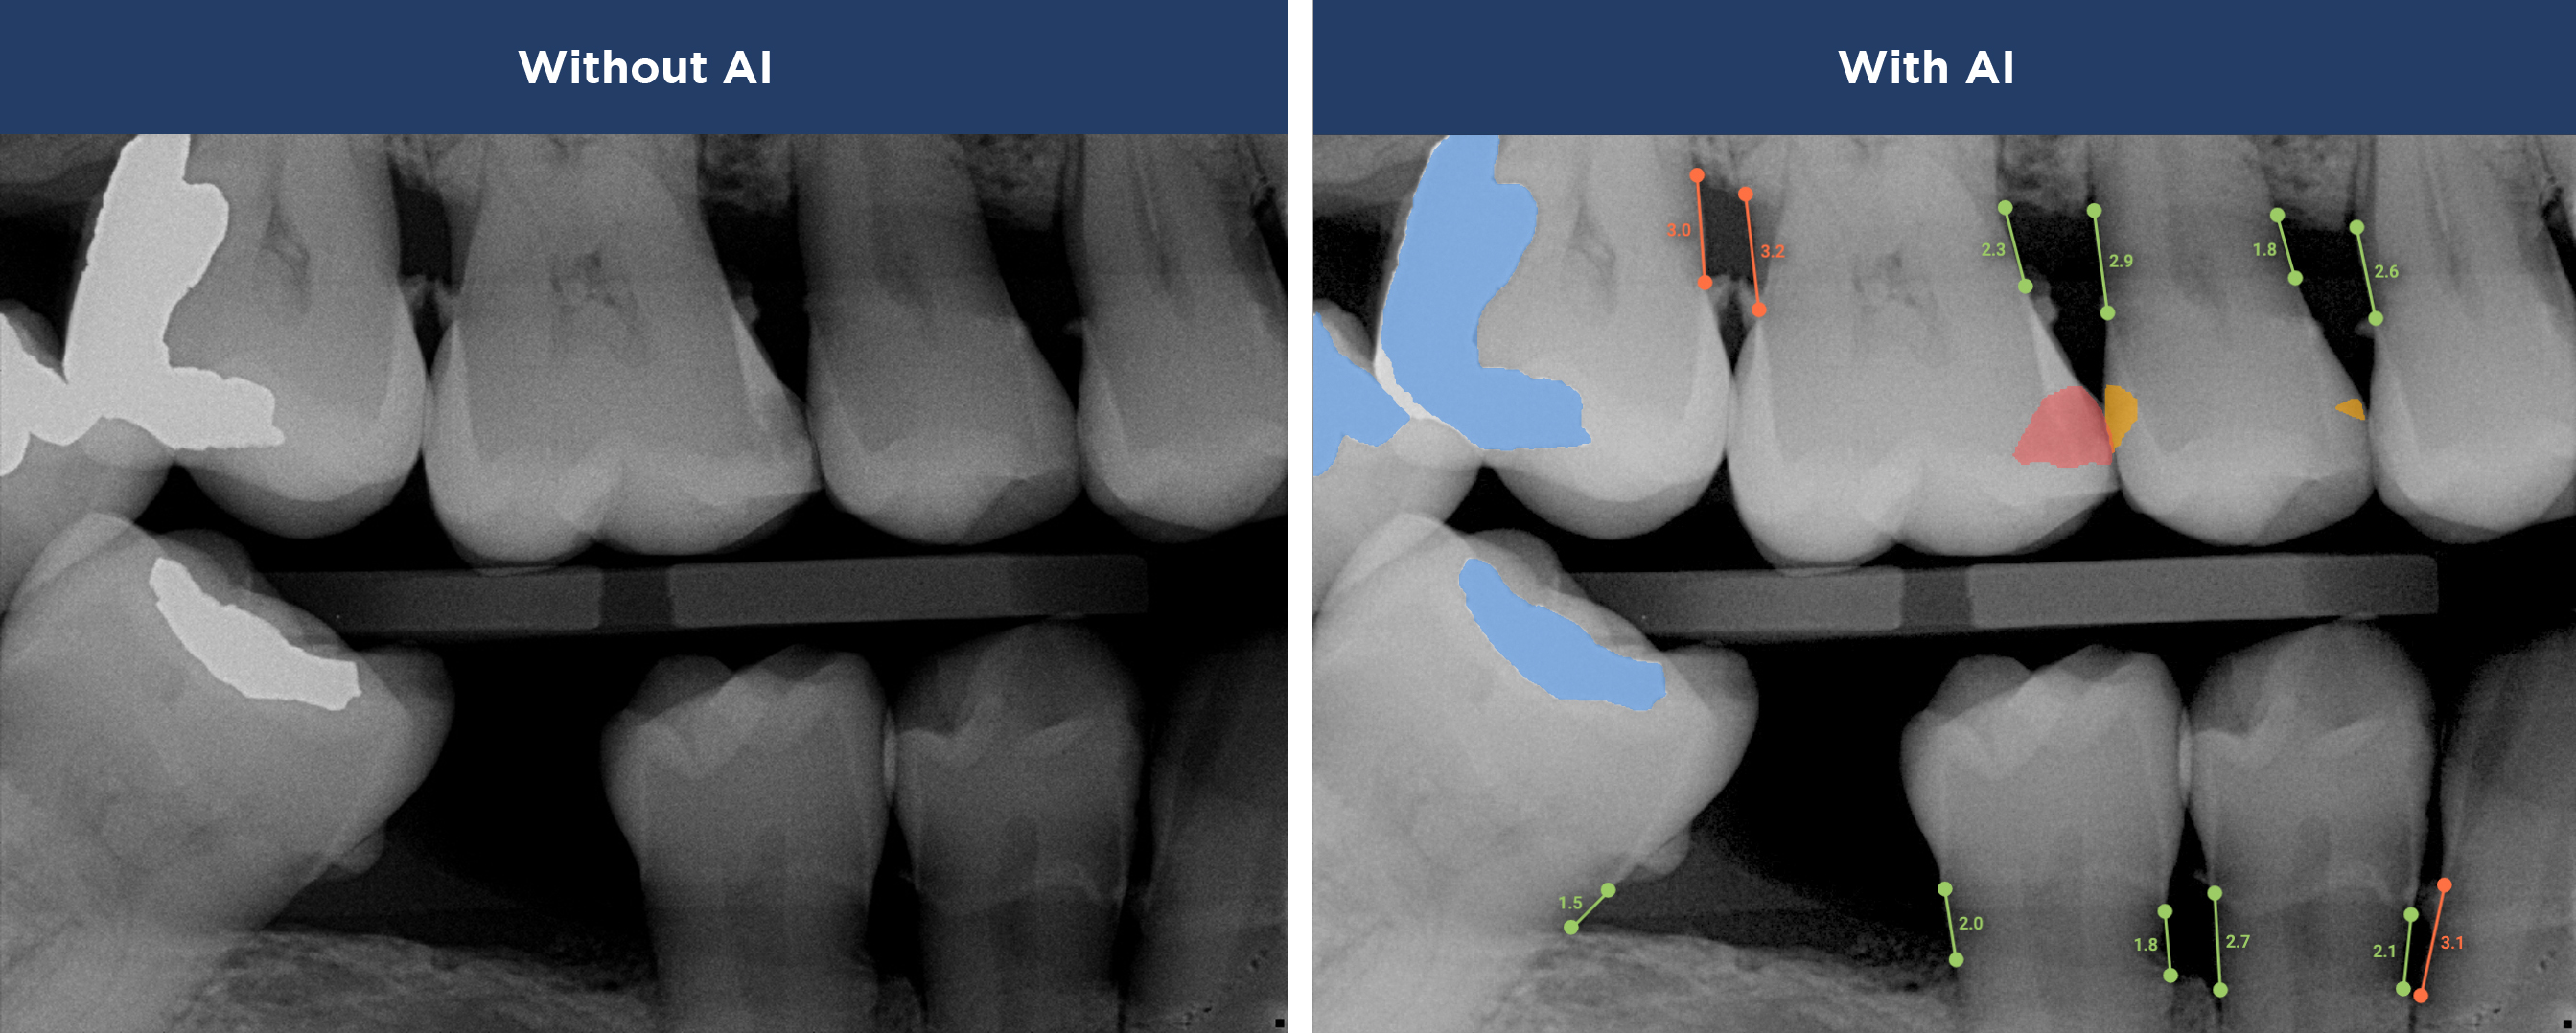

See More with AI

Overjet’s artificial intelligence technology transforms traditional black-and-white X-rays by adding a layer of data that instantly outlines decay (cavities) and measures bone loss. This makes it easy for you to see your results alongside your dentist.  It’s like getting a second opinion delivered instantly. With Overjet’s analysis and easy-to-read presentation, you will have the information you need to make an informed decision about your oral health. Together, we’ll review your findings and discuss the best steps to take to achieve your goals.